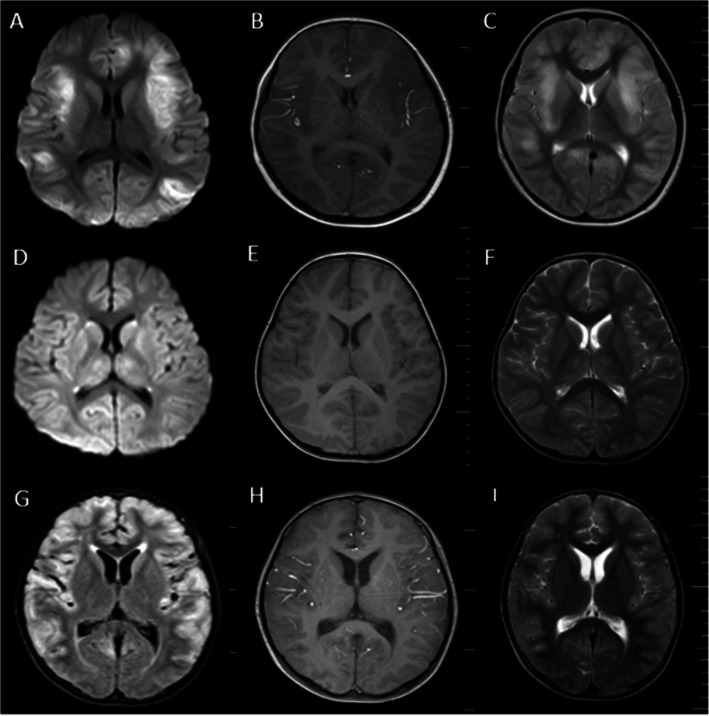

Results: The cohort comprised 75% males, with a median age of 4.5 years; all patients presented with fever and altered consciousness and required PICU admission for severe neurological symptoms. Two patients developed encephalitis sequelae and epilepsy. Abnormal electroencephalography and brain magnetic resonance imaging findings were observed in 90.9% (10/11) and 72.7% (8/11) of the patients, respectively. Five patients required ventilator support due to central respiratory failure (four invasive and one noninvasive). One patient underwent plasma exchange, while another received continuous renal replacement therapy. All patients were treated with acyclovir and immunomodulatory therapy. Four patients had poor prognoses, including one 9-year-old male who died and one 9-year-old female who was diagnosed with febrile infection-related epilepsy syndrome and remained in a coma with a Modified Rankin Scale score of 5 at the 6-month follow-up.